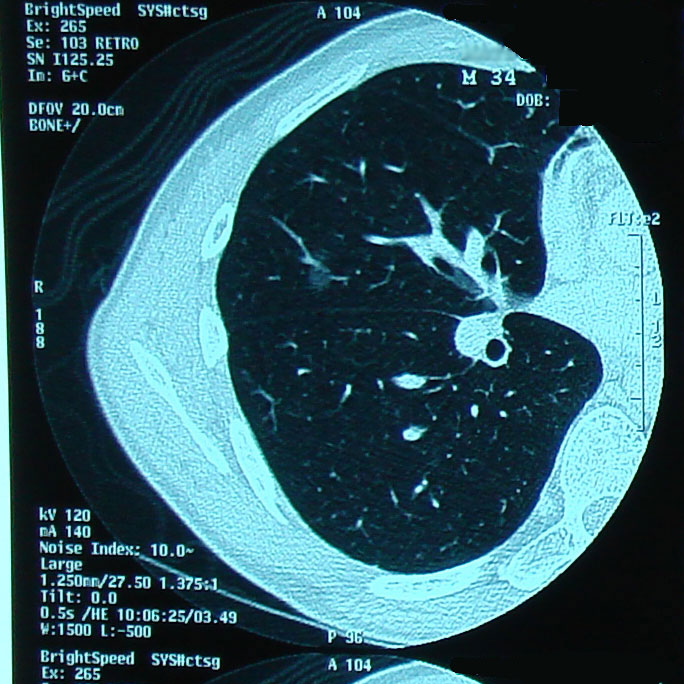

が、現実は仕事も忙しい時期であり、そう簡単には希望の生活にはならない。 今週で仕事の大きな山が一つ片付く。それ以降は、もう体に負担のかかる生活はしたくないものだ。 8月は70時間近い残業をしている。9月は52時間。 目標とする、希望する、残業時間は20時間以内である。 次回CTは11/17である。 この1ヶ月の生活で影には消えていただきたいと思う。 マーカー類はすべて正常で問題なし。 リンパ節も変化なし。 だが、肺に薄い影あるとこのとこ。本当に薄ーい。わかるかなぁ。。。 ちなみに、直ちに転移再発というわけでもなく、放射線科の意見では「違う」とのこと。 「違う」だろうけど念のため心配なので2ヵ月後に再検査ということにした。 午前中はやや心理的に混乱したな、、、 なにしろリンパの次は肺、その次は脳というのが転移の順番である。 そりゃ頭の中がぐちゃぐちゃになりますよ。 でもまぁ「違う」だろうとの判断が出てるし、マーカーも陰性だし。 最近忙しかったのがよろしくなかったかも。 体が「このままの生活じゃ危ないよ」と危険信号を出したのかな。 と嫁と話をしました。 実際問題、今自分ができることと言えば、結局生活習慣の改善くらいなので、それを実践します。